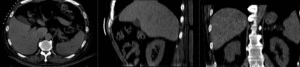

this is the intra-op CT reference image. All images are aligned into this space lleft this is the pre-op MRI we seek to align with the intra-op CT

fixed image/target moving image

• reference/fixed : pr-op CT, 0.95 x 0.95 x 5 mm voxel size

• moving: intra-op MRI, 0.78 x 0.78 x 2.5 mm axial,